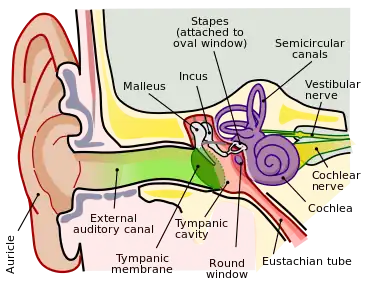

In the anatomy of humans and various other tetrapods, the eardrum, also called the tympanic membrane or myringa, is a thin, cone-shaped membrane that separates the external ear from the middle ear. Its function is to transmit sound from the air to the ossicles inside the middle ear, and then to the oval window in the fluid-filled cochlea. Hence, it ultimately converts and amplifies vibration in the air to vibration in cochlear fluid.[1] The malleus bone bridges the gap between the eardrum and the other ossicles.[2]

Orientation and relations

The tympanic membrane is oriented obliquely in the anteroposterior, mediolateral, and superoinferior planes. Consequently, its superoposterior end lies lateral to its anteroinferior end.

Anatomically, it relates superiorly to the middle cranial fossa, posteriorly to the ossicles and facial nerve, inferiorly to the parotid gland, and anteriorly to the temporomandibular joint.

Regions

The eardrum is divided into two general regions: the pars flaccida and the pars tensa.[3] The relatively fragile pars flaccida lies above the lateral process of the malleus between the Notch of Rivinus and the anterior and posterior malleal folds. Consisting of two layers and appearing slightly pinkish in hue, it is associated with Eustachian tube dysfunction and cholesteatomas.[4]

The larger pars tensa consists of three layers: skin, fibrous tissue, and mucosa. Its thick periphery forms a fibrocartilaginous ring called the annulus tympanicus or Gerlach's ligament.[5] while the central umbo tents inward at the level of the tip of malleus. The middle fibrous layer, containing radial, circular, and parabolic fibers, encloses the handle of malleus. Though comparatively robust, the pars tensa is the region more commonly associated with perforations.[6]

Umbo

The manubrium (Latin: handle) of the malleus is firmly attached to the medial surface of the membrane as far as its center, drawing it toward the tympanic cavity. The lateral surface of the membrane is thus concave. The most depressed aspect of this concavity is termed the umbo (Latin: shield boss).[7]

Nerve supply

Sensation of the outer surface of the tympanic membrane is supplied mainly by the auriculotemporal nerve, a branch of the mandibular nerve (cranial nerve V3), with contributions from the auricular branch of the vagus nerve (cranial nerve X), the facial nerve (cranial nerve VII), and possibly the glossopharyngeal nerve (cranial nerve IX). The inner surface of the tympanic membrane is innervated by the glossopharyngeal nerve.[8]